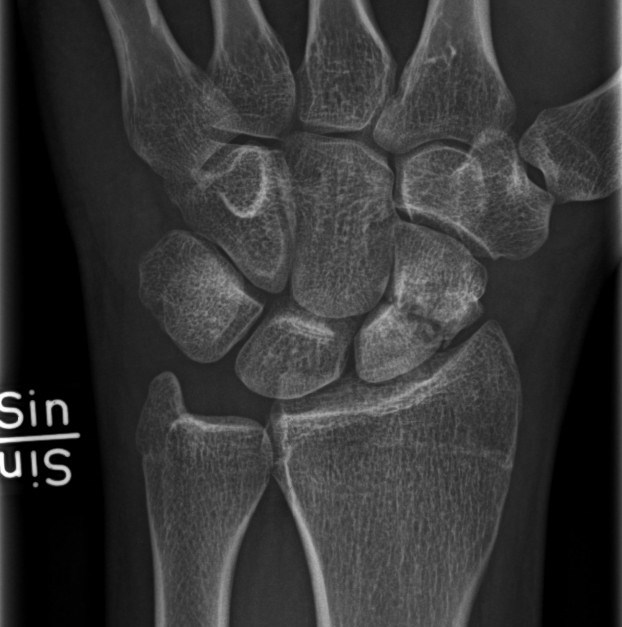

Scaphoideumfraktur

Symtom

Palpationsömhet i fossa Tabatiére, smärta vid axialt kompression av tummen samt vid dorsalextension respektive radialdeviation av handleden.

Drabbar ofta yngre individer i samband med sportutövning eller efter annat kraftigt dorsalextensionsvåld. Frakturen är ofta svår att identifiera på slätröntgen varför upprepade undersökningar och/eller CT/MR kan behövas.

Scaphoideum är dåligt vaskulariserad och ofta läker dessa frakturer (ffa proximala polfrakturer) långsamt; 3 månader i gips är normaltid! Gipsen skall immobilisera tumbas, handled och begränsa armens pro-supination. Utebliven läkning (pseudartros) är relativt vanligt och risken ökar om frakturen inte immobiliseras från skadetillfället.

Vid misstanke om scaphoideumfraktur (adekvat trauma, ömhet i fossa Tabatiére)

- Immobilisera i scaphoideumgips även om röntgen bedöms normal.

- Beställ då röntgenkontroll (utan gips) efter 10-14 dagar! Om röntgen är u a även efter 2 veckor, men status kvarstår: ordna snar MR- eller CT-undersökning!

Om skadan missas leder den mycket ofta till pseudartros och senare artros. En smärtsam pseudoartros kräver ofta att man tillför ben från crista illiaca vid operation och vid en handledsartros krävs någon typ av steloperation eller annat större ingrepp.

Det är tyvärr vanligt att frakturen missas då patienten kan uppleva symtomen som en distorsion, men det är också ganska vanligt att det missas av den undersökande doktorn. Detta sammantaget (s.k. 'patient's and doctors’ delay') innebär tyvärr att pseudoartrosoperationer är ganska vanliga.